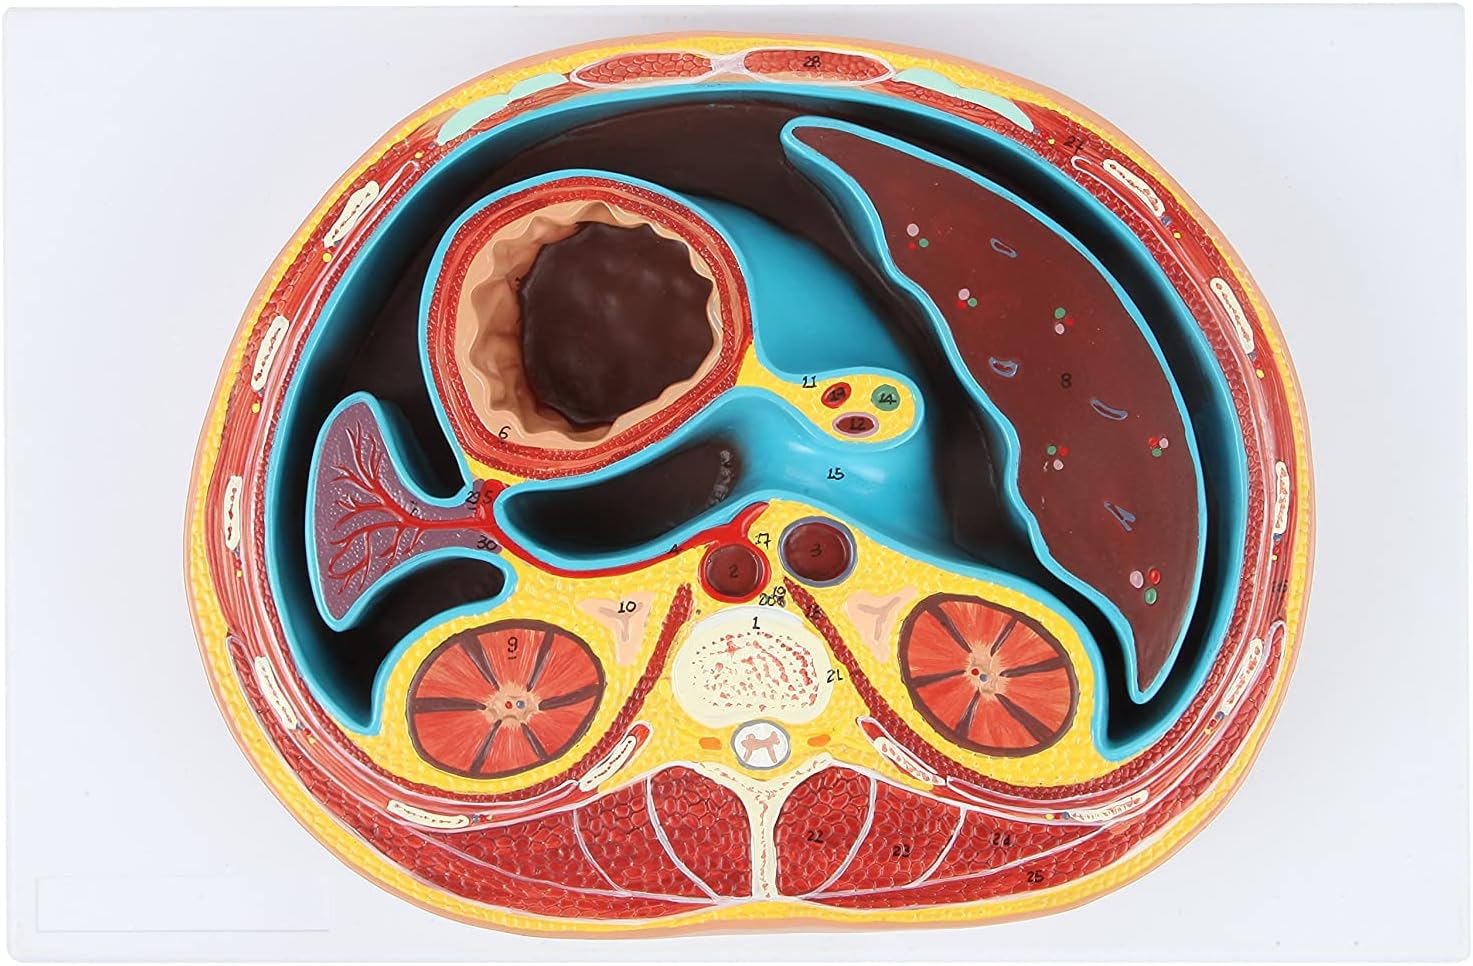

Human Anatomy Model of Abdominal Cross Section Lumbar Vertebra Human Thoracic Model Cross-Sectional Model of The Thoracic Cavity Urinary Teaching Anatomy Model

Anatomy Model of Abdominal Cross Section

The cross-sectional model of the thoracic cavity shows about the height of the T8 lumbar vertebra.

Anatomical Standard:According to the normal anatomical posture, the flat mediastinum is used as a cross-cut design, and the height of the eighth thoracic vertebra is shown in detail.